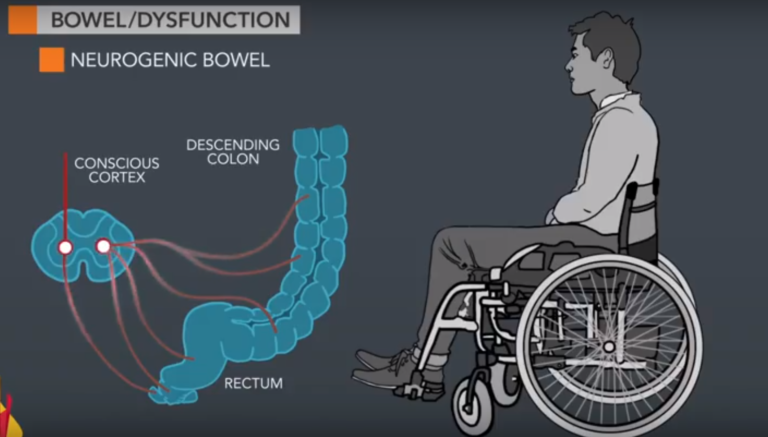

Bài viết trình bày về rối loạn kiểm soát bàng quang do thần kinh

Bài viết trình bày về rối loạn tiểu do nguyên nhân thần kinh (bàng quang thần kinh), từ sinh lý, phân loại, nguyên nhân, lượng giá, các chiến lược can thiệp và đặc điểm của rối loạn tiểu trong những bệnh lý thường gặp.